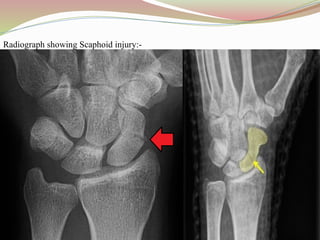

Radiograph showing Scaphoid injury:-